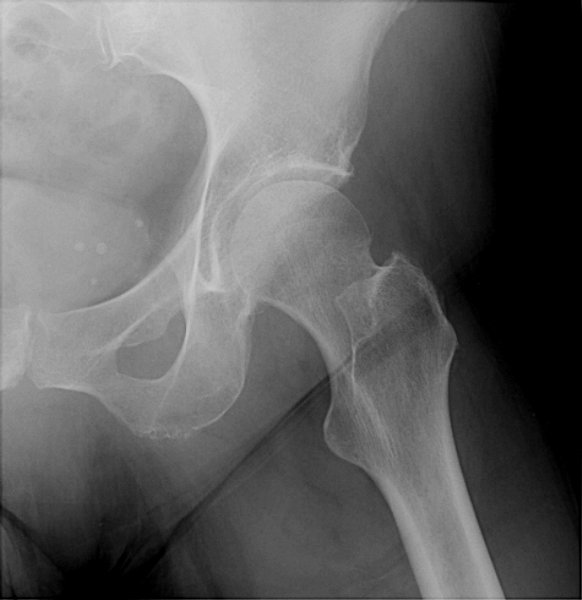

Return to Femoral Neck Fracture